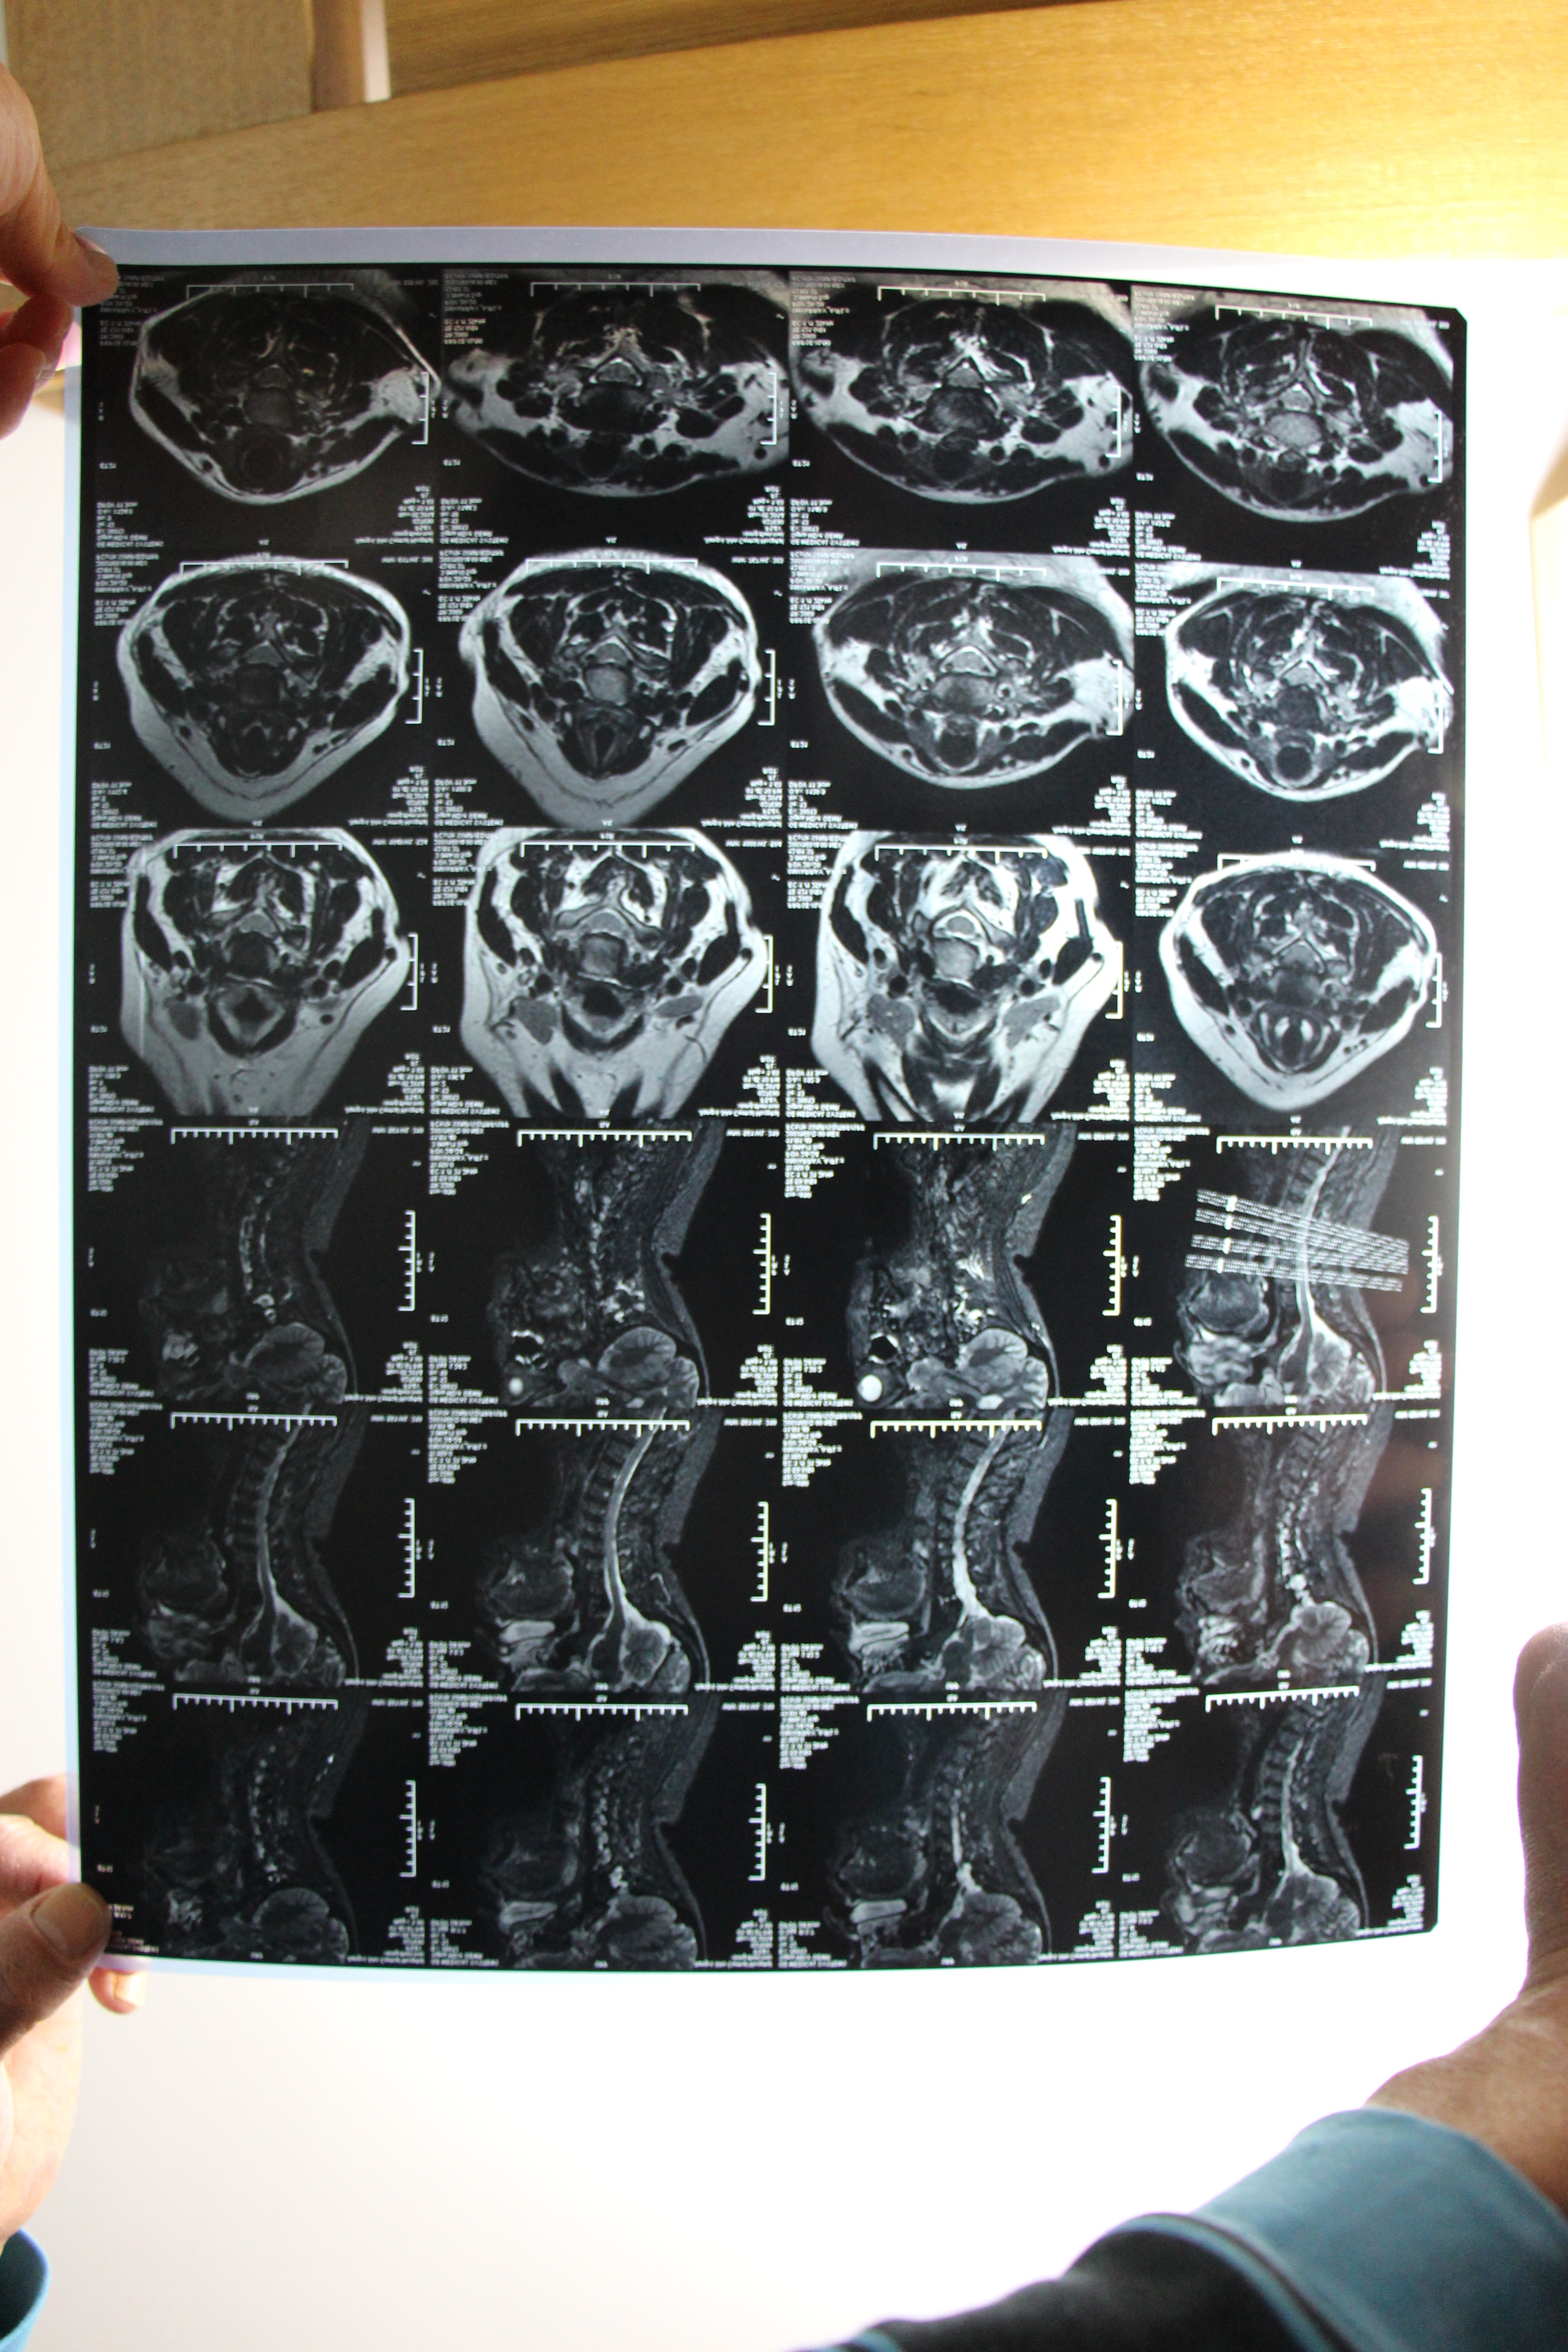

我是云南玉溪峨山县的,在乡镇上工作,今年36岁。由于长期伏案,下村工作,最近2年偶尔会感觉疲劳、头晕,但休息半天会就几个月都会不头晕,去年11月做了脑部,颈椎ct和核磁共振,脑部一切正常,颈椎c5颈椎盘向后突出2mm轻度压迫硬膜囊。其它的一切正常。半年来没有头晕过。今年8月2日我去我们县中医院按摩理疗了一个星期,他们的手法比较重从第3天开始走路会突然头晕,站不稳,头向左转时头晕,没有疼痛感。在这之前我重来都不会出现站不稳情况,我的身体一直都非常健康,各项检查都好。8月9日我感觉一般的走路会头晕,就要求转院去玉溪市中医院治疗。一直住了20天,做了各种理疗、牵引、打针。感觉也住病也重。头晕、手脚一会麻一会不麻,麻的部位也不固定。在住院期间我又做了颈椎、腰椎的x片子、ct、核磁共振。后来我拿着片子到昆明云大医院看过,医生说没片子问题。让我不要治疗了回家去,平常怎么生活你还怎么生活。从8月25号回家后在家拍球、游泳。不动的时候头一般不头晕,就是走路时间一长会走不稳,手脚一会不麻一会麻。头上的筋会时不时酸胀。人平坦的时候症状会减轻和消失,量血压一直都正常。我们这里有温泉,只要到水里就感觉轻松,怎么活动头都不会晕,从水里起来感觉身子重,这几天感觉舒服一点,就是病情一会好一会不好。能帮我看看吗。全家人为了我这个病整日不快乐,我也整日少言寡语。整个家庭的生活以前是快乐的。现在是个什么样我也说不清。都为我心痛,心酸吧。我还能恢复健康吗。 2010年8月2号前36年我从来没有因为身体健康住过医院。 想得到怎样的帮我的病能治疗好吗,怎么治疗。一定帮帮我回家到现在感觉好一点。就是一低头头部的经脉就发麻,酸麻。颈椎片子做了x、ct、mri。脑部mri、cta正常。跑了许多医院看过神经内科、神经外科看过。 我是颈椎病吗,帮我看看片子。我要如何治疗,在家里如何护理,还可以向平常的运动吗。医生看的多吃的药有8、9种。感觉太痛苦了。医生帮帮我好吗,我整个人都要垮了。回家到现在感觉好一点。就是头部的经脉就发麻、酸麻,低头症状多一些。能帮助我制定一个简单的家里治疗方案和锻炼方案吗。能跑步和游泳锻炼吗。能和你经常联系吗。为盼。